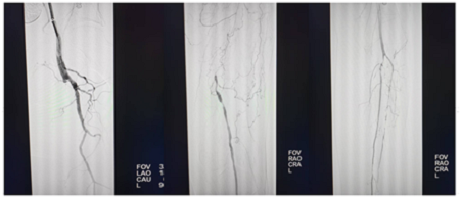

血管外科主任崔文军,副主任医师安乾及主治医师司江涛、王广华,结合丰富案例经验,在术前对手术细节进行反复打磨,确定最佳手术方案。经过3小时协同攻坚,患者股浅动脉及膝下动脉全程开通,并且造影显影良好,患者疼痛感即刻消失。

微信图片_20250225185507

术后造影血管通畅,左足皮温皮色明显好转